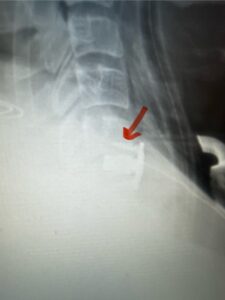

Fig. 4: Intraoperative lateral cervical x-ray demonstrating anterior cervical construct in good position at C 5 6 (red arrow)